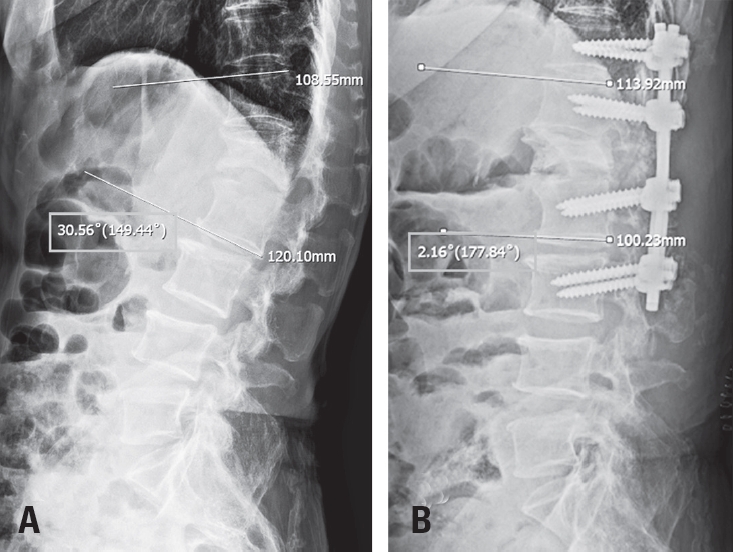

Fig. 1.

Pre-and post-operative plain radiography. (A) Preoperative plain radiography demonstrates a local kyphotic angle of 30° between T12 and L2. (B) Postoperative plain radiography shows a correction of the local kyphotic angle to lordotic 2° between T12 and L2. So, its change of the cobb angle between T12 and L2 was nearly 32°.

Fig. 1. Pre-and post-operative plain radiography. (A) Preoperative plain radiography demonstrates a local kyphotic angle of 30° between T12 and L2. (B) Postoperative plain radiography shows a correction of the local kyphotic angle to lordotic 2° between T12 and L2. So, its change of the cobb angle between T12 and L2 was nearly 32°.

Plain radiographs demonstrated an L1 compression fracture with focal kyphosis. Magnetic resonance imaging (MRI) revealed findings consistent with TCS associated with a lipomyelomeningocele, along with the L1 compression fracture (Fig. 1). Preoperative electrodiagnostic studies showed the bilateral absence of H-reflexes in the tibial nerves and prolonged P40 latency on tibial somatosensory evoked potentials (SSEP), consistent with myelopathy.

The patient tolerated the procedure well without any intraoperative adverse events or signal changes in IONM. Immediate postoperative plain radiographs demonstrated a reduction in local kyphosis by approximately 28 degrees and a decrease in the spinal column height of approximately 10 mm at the osteotomy site (Fig. 2). MRI obtained on postoperative day 2 revealed distinct interval relaxation of the spinal cord compared with preoperative images, indicating an effective release of longitudinal tension (Fig. 4).